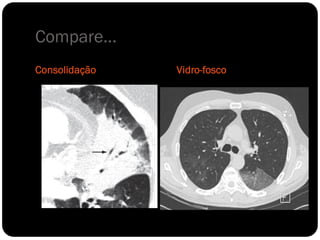

Compare...

Consolidação   Vidro-fosco

Conceitos

 Atelectasia: ausência do ar alveolar;

 Consolidação: substituição do ar alveolar (não há redução de

volume);

 Quando ocorre essa consolidação os brônquios em seu

interior podem tornar-se visíveis – broncograma aéreo.

Vidro fosco

 Opacidade observada na TC, pode ser decorrente tanto de

alteração do espaço aéreo quanto do interstício.

 Alvéolos ou interstício ocupados parcialmente por processo

patológico (líquido, células, exudato); Resoluação da TCAR

não é suficiente para definir a imagem;